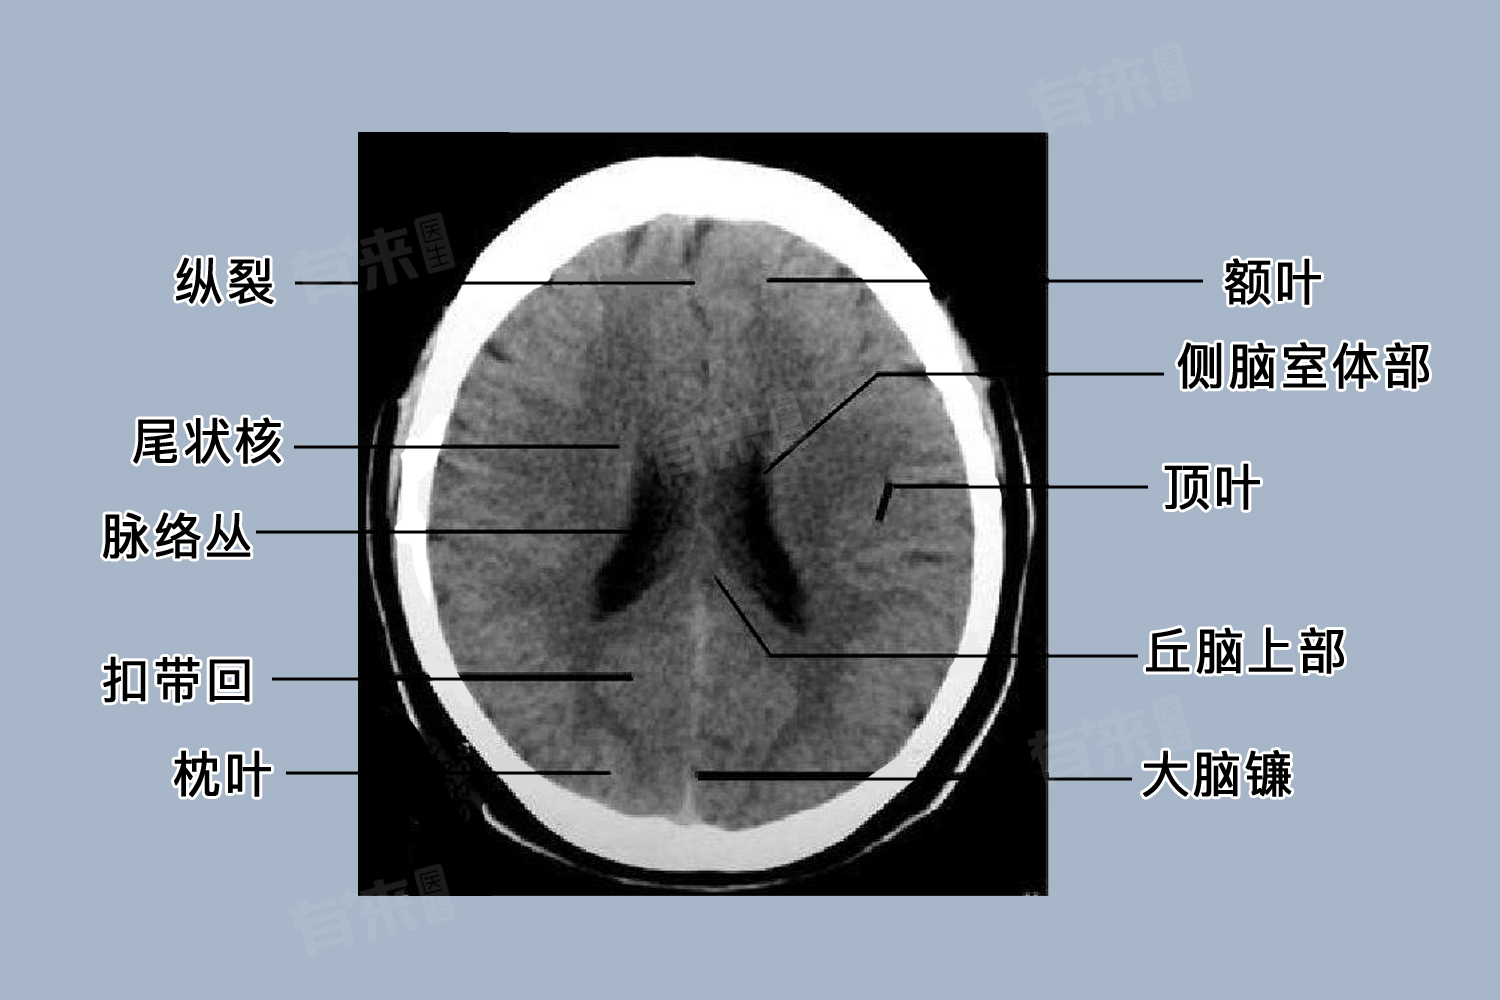

脑CT检查是一项重要的辅助检查手段,对于脑部疾病的诊断和治疗具有重要意义,患者在选择检查时不应仅仅关注价格,还应综合考虑医院的专业水平、设备质量以及医生的经验等因素,以确保检查结果的准确性和可靠性,从而为后续的治疗提供有力依据。